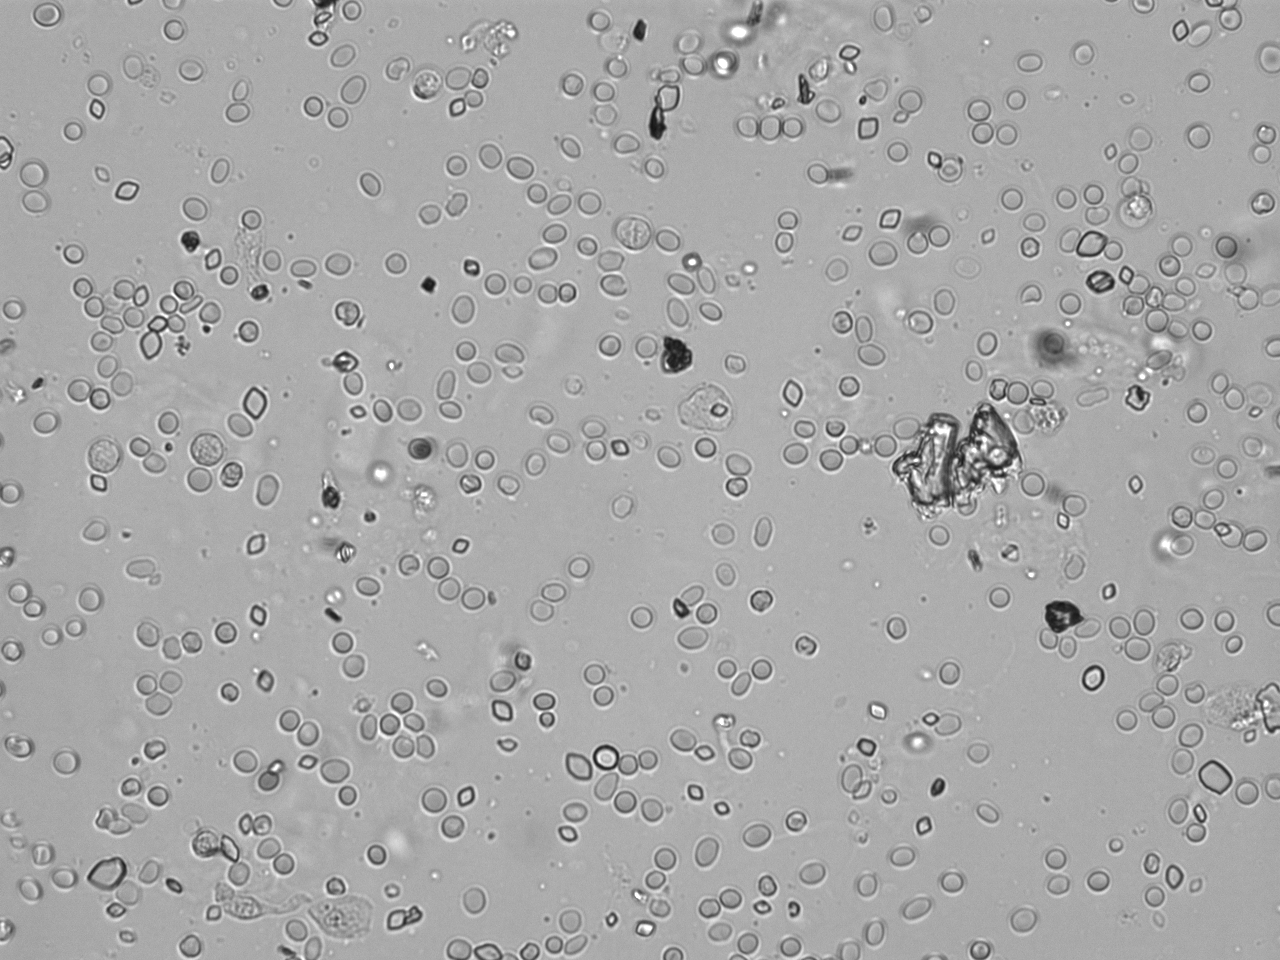

Urin-Feature: Harnskristalle_Rhomboid